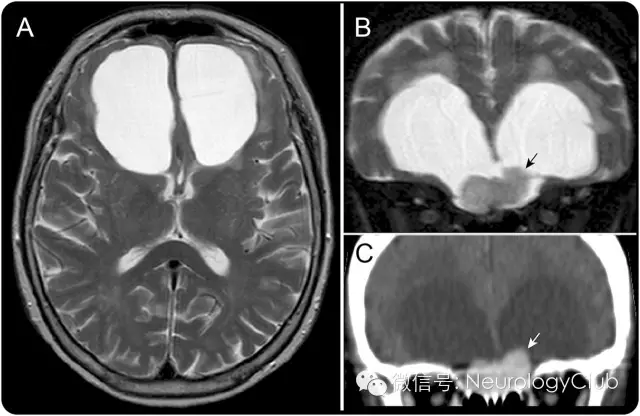

73岁女性,表现为进行性冷漠,健忘和步态障碍6月。神经系统查体提示注意力不集中,记忆缺陷和宽基步态。因患者钆过敏,故只能行非强化磁共振检查。MRI和增强CT提示双侧额叶对称性囊肿(图1A)以及前颅底结节状病灶(图1B和C)。手术证实为鸡冠部来源的脑膜瘤(图2A)。术后患者症状改善,囊肿缩小(图2B)。

(图1:[A]横断位和[B]冠状位T2WI可见对称性双侧额叶大囊肿和一横跨于筛板上的等信号结节;[C]增强CT扫描可见结节状病灶均匀强化。鉴别诊断包括脑膜瘤,嗅母细胞瘤和血管外皮细胞瘤)

囊性脑膜瘤可分为瘤内型,实质内型,蛛网膜下/蛛网膜上型等。囊性变偶可见于颅底脑膜瘤,通常为单侧。对称性双侧囊肿罕见。